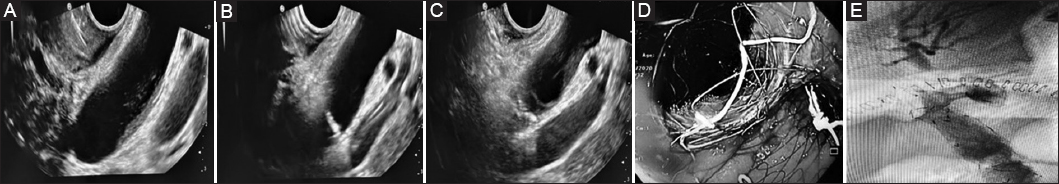

A total of 15 patients (8 male, median age 72, range 55-84 years) underwent EUS-biliary drainage with ECE-LAMS placement. Demographic characteristics, causes of biliary obstruction and of previous ERCP failure are summarized in Table 1. The median CBD diameter was 14.5 mm (range 13-24). An 8×20 mm LAMS with a 23 mm flange and a 10×20 mm LAMS with a 25 mm flange were used in 13 and 2 patients, respectively. The procedure was technically successful in all patients. The biliary duct was reached through a trans-bulbar approach in 13 patients and a transduodenal approach in the remaining cases. The median procedure duration was 12 min (range 10-18). The phases of the procedure are depicted in Fig. 1. In 6 (40%) patients there was also a neoplastic duodenal obstruction that was treated with a duodenal u-SEMS. More specifically, in 2 patients duodenal stenting was performed 1 month before the choledochoduodenostomy, because of a local advanced duodenal adenocarcinoma that later caused obstructive jaundice. In both these patients, LAMS deployment was performed using a transduodenal approach, with the SPAXUS SEMS placed proximally to the duodenal stent in one patient and inserted through the mesh network of the uncovered duodenal stent in the other. The remaining 4 patients were treated with duodenal stenting and biliary drainage in the same session, using a trans-bulbar approach. The median hospitalization time was 6 days (range 2-17). Clinical success was eventually achieved in 14 (93.3%) patients, whose mean bilirubin level was 2.55±3 mg/dL after 2 weeks.

Figure 1 (A) Endoscopic ultrasound image showing dilated choledochal biliary duct (CBD); (B) puncture of the CBD; (C) deployment of distal flange of a lumen-apposing metal stent in the CBD lumen; (D) endoscopic check after stent placement; (E) final cholangiography with regular biliary outflow